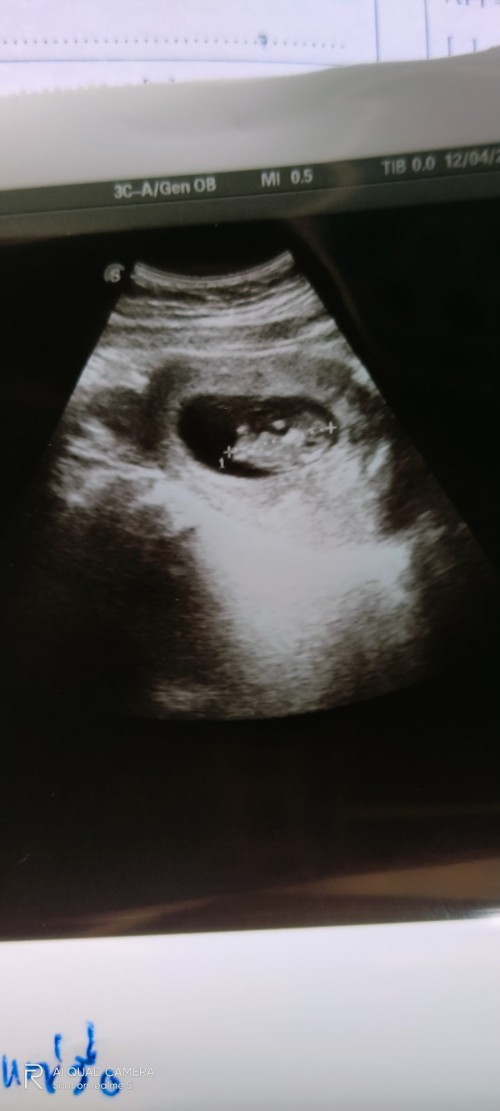

ท้องแรกค่ะ 9w 2.35 cm. ค่ะ

3เซนจ้า มาเป็นคู่😆